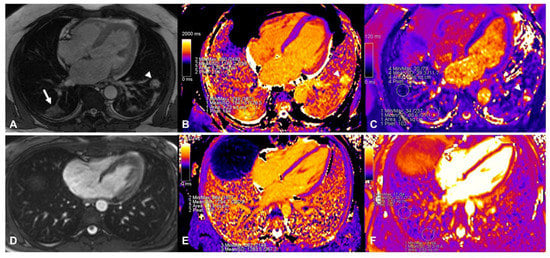

| Lung T1 mapping | |||

| Global | 1278 (1238, 1313) | 1149 (1107, 1249) | 0.003 |

| Remote | 1238 (1165, 1337) | 1152 (1114, 1249) | 0.088 |

| Affected | 1375 (1220, 1580) | 1201 (1130, 1270) | 0.016 |

| Lung T2 mapping | |||

| Global | 38 (36, 49) | 34 (28,39) | 0.040 |

| Remote | 29 (27, 35) | 33 (27, 41) | 0.797 |

| Affected | 70 (55, 82) | 30 (28, 40) | 0.001 |